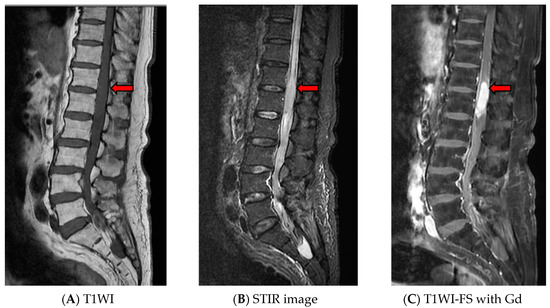

Tuberculoma of the conus medullaris was suspected due to the patient having very high CSF-ADA levels [4]. Since Thailand is an endemic area of tuberculosis, we do not routinely use tuberculin skin test or QuantiFERON-TB Gold test for diagnosis of active tuberculous infection. The patient was treated with a combination of antituberculous drugs (isoniazid (I), rifampin (R), pyrazinamide (Z), ethambutol (E)), for two months, followed by IR for eight months, and a six-week course of steroids. The dull ache gradually disappeared, and motor power improved slightly. A follow-up MRI of the LS spine at the 10th month of treatment revealed a marked decreased in the size of the lesion to 0.37 × 0.53 cm. Treatment with IR drugs was administered for eight more months. The total duration of treatment was, thus, 18 months. A follow-up MRI of the LS spine revealed that the lesion had completely disappeared (Figure 2). At two years follow-up after completion of antituberculous therapy, the motor power of the left leg improved to grade 2–3/5, and the patient has been on permanent suprapubic cystostomy.

Figure 2. Magnetic resonance imaging of the lumbosacral spine at the 16th month of treatment showing complete resolution of the lesion.